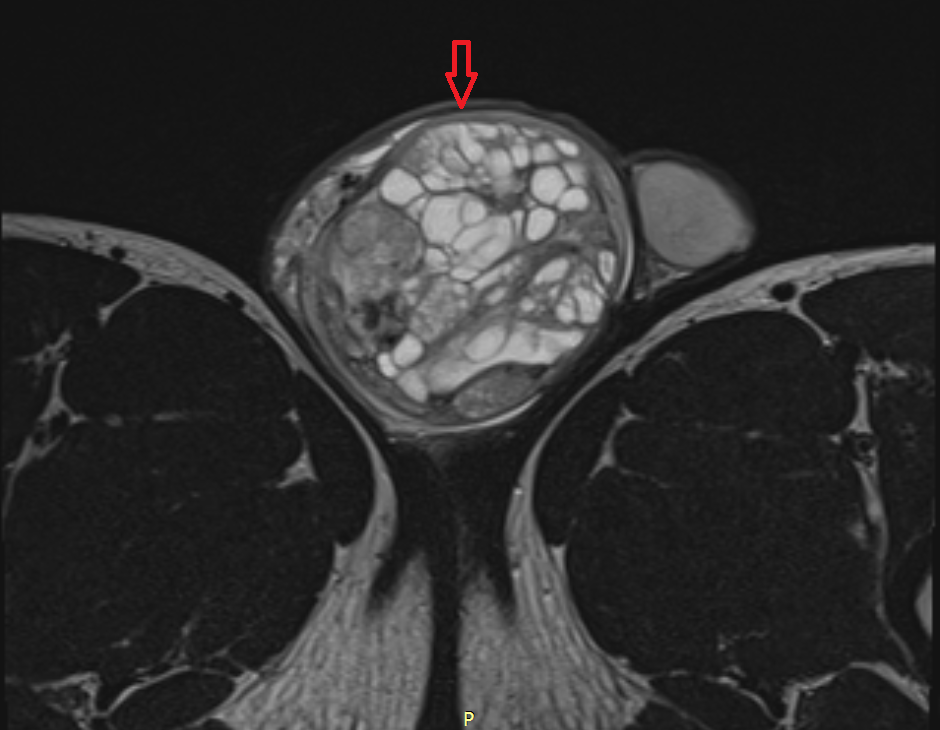

Яичко

Первичные образования в яичках (они называются тестикулярные) в детском возрасте диагностируются редко. Чаще всего их обнаруживают у детей в возрасте до 2-х лет, при этом 25% – уже при рождении.

Risunok2b.pngРисунок 2. – семинома яичка: а - макропрепарат, б - МРТ.

По гистологической (то есть тканевой) структуре это наиболее часто новообразования желточного мешка либо доброкачественные тератомы.

Второй пик возникновения опухолей яичка – пубертат. В этот период растет частота заболеваемости злокачественными тератомами. Семиномы встречаются у детей крайне редко.

Припухлость яичка, которая быстро увеличивается и не причиняет ребенку боли, чаще всего обнаруживается родителями. 10% таких новообразований сочетается с «водянкой яичка» (мед. «гидроцеле») и другими врожденными патологиями, особенно мочевыводящей системы.

При осмотре видно плотное новообразование, бугристое, без признаков воспаления. Диагноз опухоли до операции подтверждает повышенный уровень альфа-фетопротеина (АФП).

Новообразование при этом содержит элементы желточного мешка.